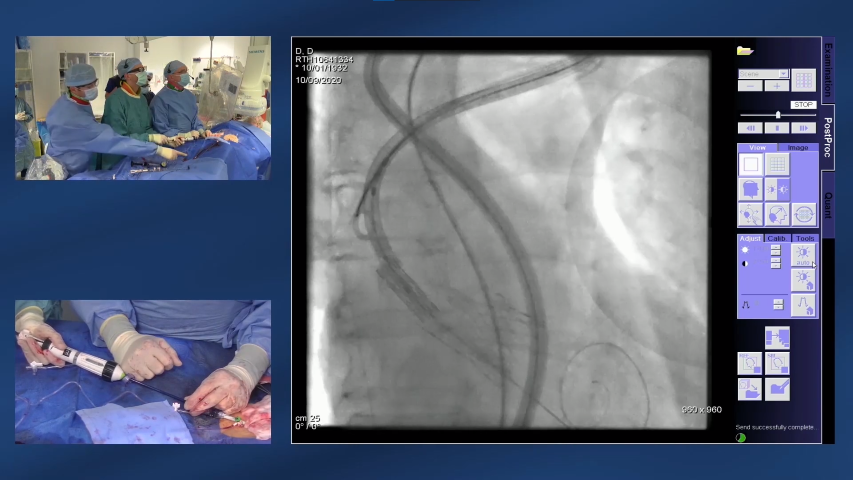

• El procedimiento de TAVI ViV es similar a una intervención TAVI inicial; la válvula fallida se utiliza para guiar la colocación de la válvula de reemplazo6

• La válvula de reemplazo se despliega gradualmente y la nueva válvula bioprotésica se fija bien en el interior de la válvula defectuosa, empujando hacia un lado las valvas de la válvula antigua6

• Se emplea angiografía para garantizar la colocación precisa de la válvula6

Observe cómo se realiza correctamente una intervención ViV. - 12 min